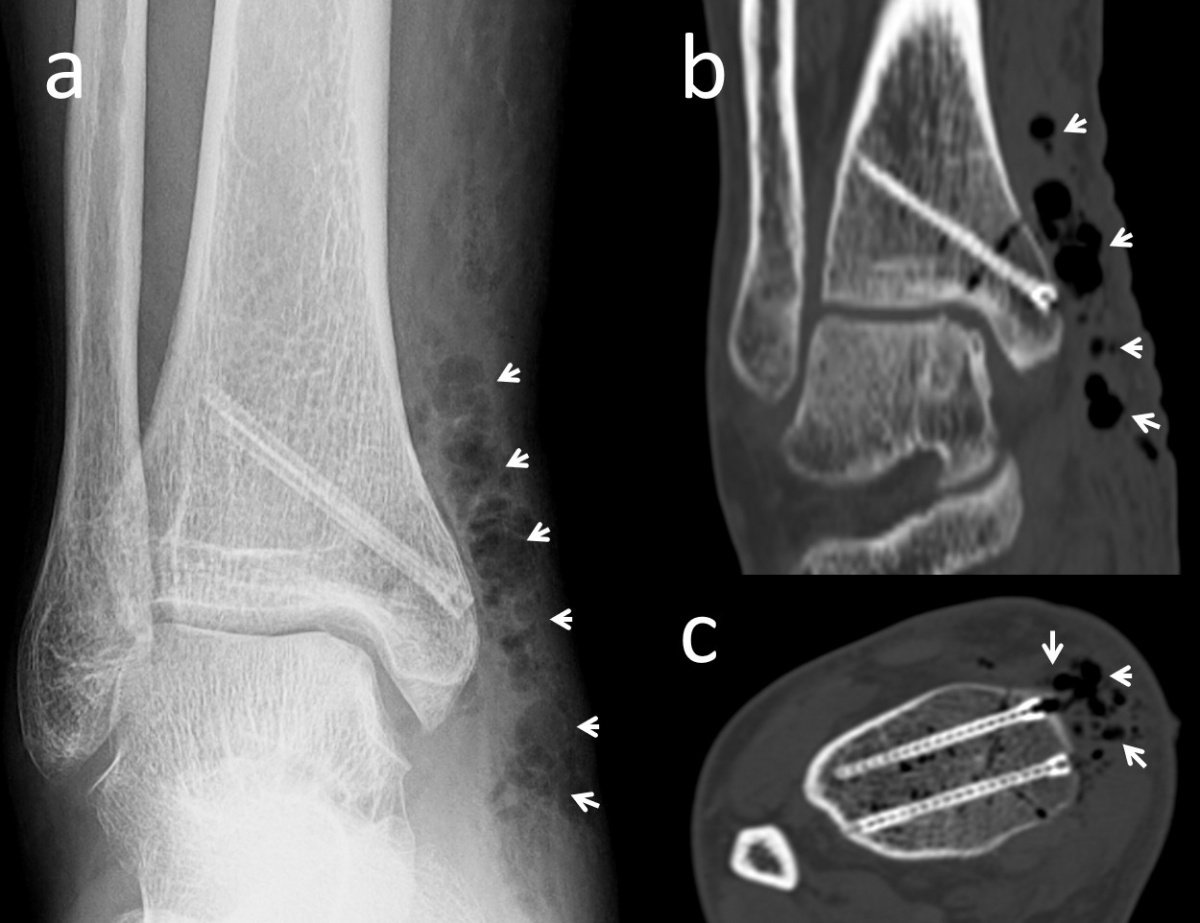

einer osteochondralen Läsion am

Talus einer Innenknöchel-Osteotomie und

Mosaikplastik unterzogen wurde. Die biplanare

Innenknöchel-Osteotomie wurde mit zwei

Magnesiumschrauben fixiert. (a) Die anterior-

posteriore Röntgenaufnahme des Knöchels

am 7. postoperativen Tag zeigt an der Operationsstelle

diffuse Gasansammlungen im

Weichgebe (weiße Pfeile). (b) Koronare und

(c) axiale CT-Aufnahmen mit sichtbarem Gas

(weiße Pfeile).

In Bezug auf die Gasbildung und Resorption zeigt die Computertomographie ähnliche Ergebnisse wie die konventionellen Röntgenaufnahmen. In der Frühphase sind sowohl die Schrauben als auch die umgebenden Gasansammlungen deutlich sichtbar (Abbildung 5). Langfristige CT-Untersuchungen zeigen, dass das Gas vollständig resorbiert wird und damit vollständig verschwindet. Die Schrauben sind bis zu ihrer Umwandlung in kortikales Knochengewebe deutlich erkennbar (Abbildung 6). Adil et al. haben nachgewiesen, dass diese Konturen vier Jahre nach der Implantation in der tomographischen Dichtemessung ähnliche Hounsfield-Einheiten aufweisen wie die umgebende Kortikalis (17). Darüber hinaus erzeugen Implantate auf Magnesiumbasis – im Gegensatz zu konventionellen Metallimplantaten wie Titanschrauben – nur minimale Metallartefakte (18-20). Für die Nachbeobachtung der Patienten stellt dies einen signifikanten Vorteil dar.